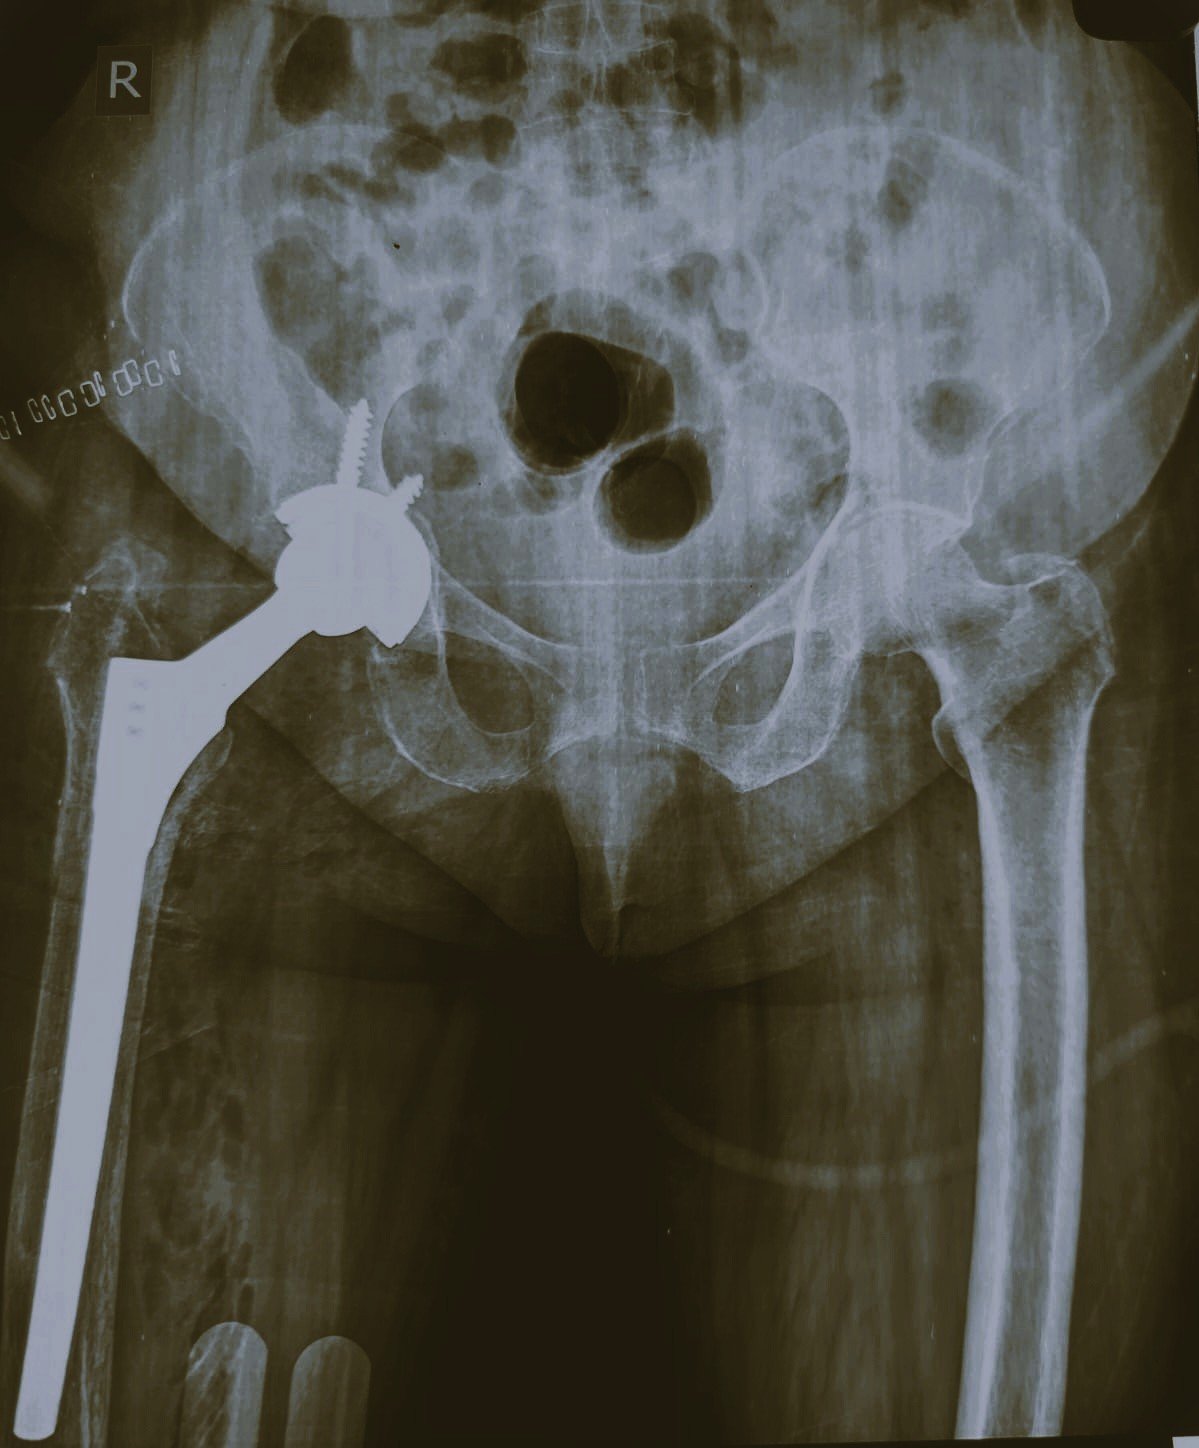

Post-Op X-Ray

Revision Long Stem THR in Aseptic Loosening of Fixed Bipolar Prosthesis

DHS Failure & Long Stem THR